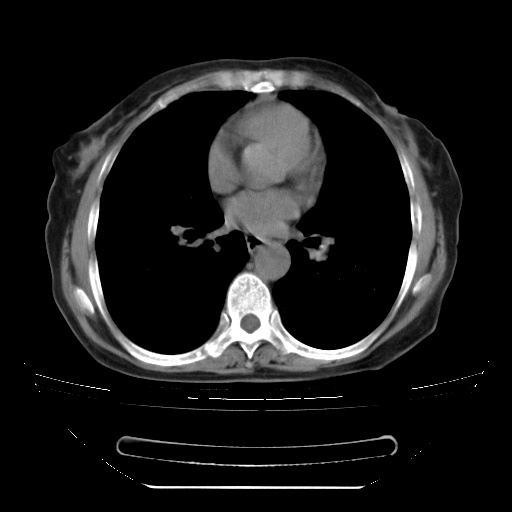

查原发灶吧,肺内转移瘤!肝内也有病灶,需强化明确。

以下是引用zsl6918在2009-3-5 23:00:00的发言:[br]查原发灶吧,肺内转移瘤!肝内也有病灶,需强化明确。

两肺内病灶呈小结节状和树芽状,纵膈的肿大的淋巴结密度不均匀,并见有钙化,考虑为两肺结核可能更大些。

两肺内病灶呈小结节状和树芽状,纵膈的肿大的淋巴结密度不均匀,并见有钙化,多形态病灶,考虑为两肺结核,肝内考虑小囊肿。

纵隔见肿大淋巴结并钙化,首先考虑结核,但感觉小结节像“挂果”征,分布位于支气管边缘,所以不排外肺泡癌,建议抗唠后复查吧?不然是癌的话,也不好治吧?化疗?

以下是引用zhw974247在2009-3-6 6:25:00的发言:[br]两肺内病灶呈小结节状和树芽状,纵膈的肿大的淋巴结密度不均匀,并见有钙化,多形态病灶,考虑为两肺结核,肝内考虑小囊肿。